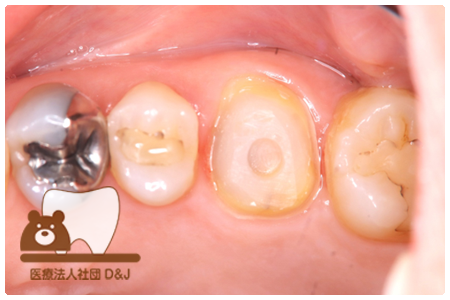

症例2フルジルコニアクラウン 左上4

治療前

治療後

63歳 男性

- 治療内容

- 根管治療の後でフルジルコニアクラウンを装着しました。

- 治療期間

- 根の治療含めて1カ月半

- 費用

- 自費

フルジルコニアクラウン:77,000円(税込)

(R8.2月時点)

- その他の治療の費用は含まれておりません。

- リスク・副作用

- 強い力が加わると割れる可能性があります。また、噛み合わせや歯ぎしりの影響で脱離することがあります。